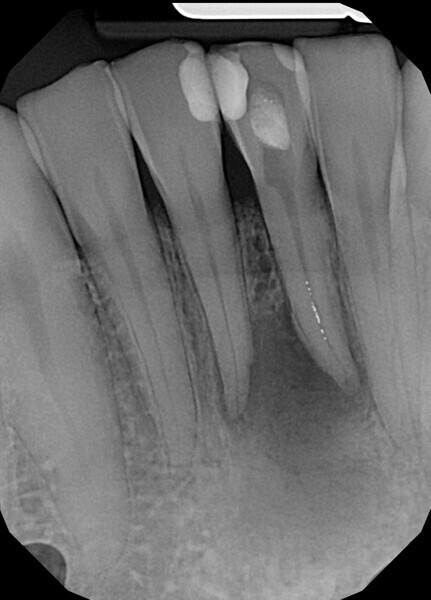

Case 4

The patient was referred to Dr Karaś’s office for non-surgical root canal retreatment of tooth #46. The tooth was symptomatic, and the radiographic examination revealed a periapical lesion around the mesial root. The periapical lesion was clearly visible, but the shape of the root canal was not clear (Fig. 22). The examination was extended by CBCT imaging. The CBCT scan revealed internal resorption in the mesiobuccal canal and an isthmus and apical inflammatory root resorption in the apical area of the mesial root (Fig. 23). A cast post and prosthetic crown were also noted.

At this stage, one of the most important decisions had to be made regarding the resorption and isthmus present in the mesial root. On the one hand, in the case of non-penetrating internal resorption, the material of choice is gutta-percha with a sealer. On the other hand, in the case of apical inflammatory root resorption, it is recommended to use mineral trioxide aggregate (MTA) or putty materials. There is no problem with using these two materials in the same root in most cases, but in this case, the canals were too narrow to use the MTA comfortably and the quality of filling of the isthmus that could be achieved was questionable.

From this point of view, a novel approach of placing a tricalcium silicate-based sealer was a promising idea. The sealer was placed in the previously described manner. The premixed sealer in the plastic syringe (Meta Biomed) was placed in the mesiobuccal canal and the syringe depressed until it filled the mesiolingual canal. The distal canal was filled separately. In each canal, pistons from the previously heated gutta-percha extruder were placed and the warm gutta-percha was slightly compacted with stainless-steel hand condensers. A periapical radiograph was taken to evaluate the quality of the obturation. The bioceramic sealer was slightly extruded through the resorbed apex into the periapical area (Fig. 36). After the obturation, the chamber and orifices were cleaned (Fig. 37). A resin core with fibre posts was placed, and the temporary pink material was removed. The patient was referred to the prosthodontist for final restoration.

The recall appointment was performed after three years. The periapical radiograph and CBCT scan revealed healing of the periapical tissue and no resorption of the bioceramic sealer (Fig. 38). The tooth remained asymptomatic.